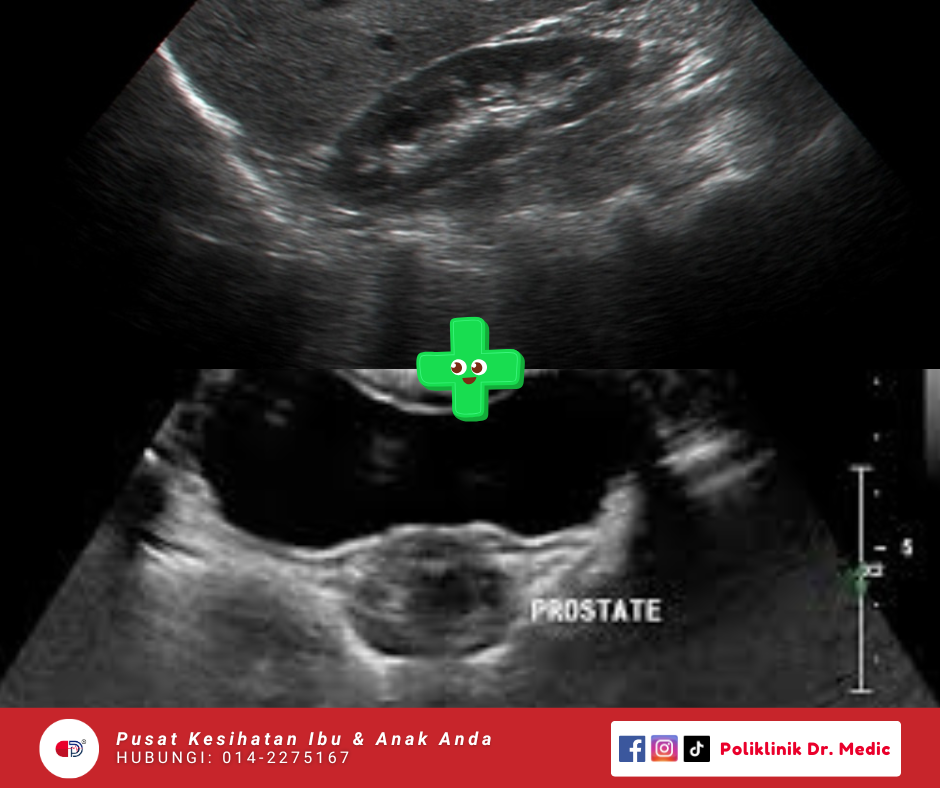

KUB + Prostate Scan

Pemeriksaan untuk tengok keadaan buah pinggang, pundi kencing, salur kencing dan kelenjar prostat. Sesuai untuk kesan batu karang, masalah kencing tak lawas, atau bengkak prostat.

RM120